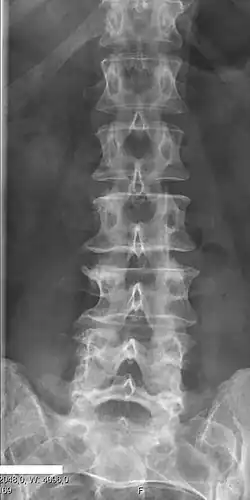

Block vertebrae

Block vertebrae occur when there is improper segmentation of the vertebrae, leading to parts of or the entire vertebrae being fused. The adjacent vertebrae fuse through their intervertebral discs and also through other intervertebral joints so that it can lead to blocking or stretching of the exiting nerve roots from that segment. It may lead to certain neurological problems depending on the severity of the block. It can increase stress on the inferior and the superior intervertebral joints. It can lead to an abnormal angle in the spine, there are certain syndromes associated with block vertebrae; for example, Klippel–Feil syndrome. The sacrum is a normal block vertebra.[8]